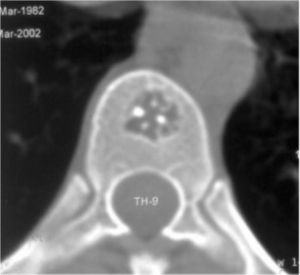

МРТ3

Рис. №3. КТ Th9 позвонка. Поражение гемангиомой части тела Th7 позвонка.